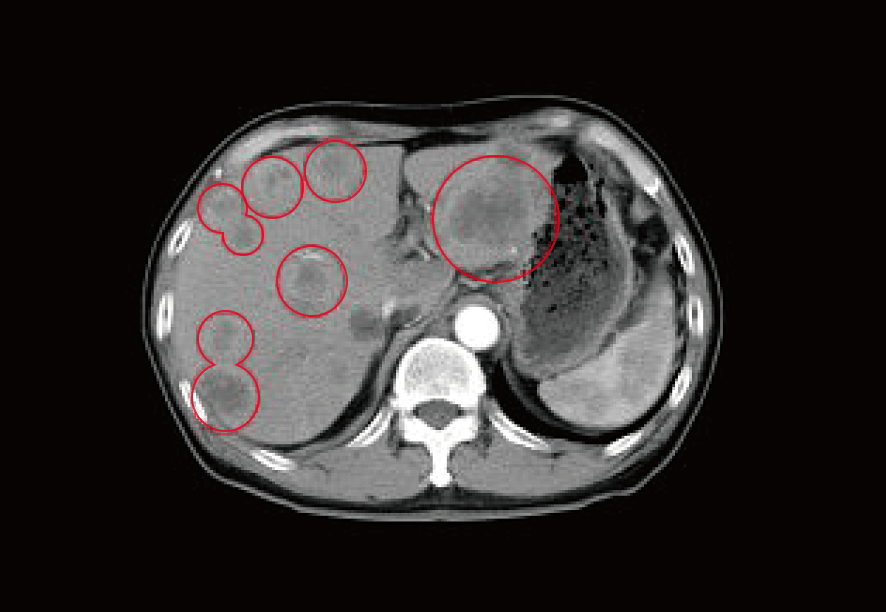

治療前CTでは肝臓全域に広がる肝転移病巣を認めている。

この時点で肝転移したがん腫瘍も数十カ所に増え、腫瘍マーカーも著しい上昇を伴っていた。 即座にがん免疫の状況を詳細に調べる高度精密血液検査システム「リスクチェッカー」を実施。

一見経過は順調そうに見えたが、一年経過時点で肝臓に多発性の転移がんが出現。

やむなく延命を目指し、抗がん剤を行うが著効なく、徐々に病状は進行。